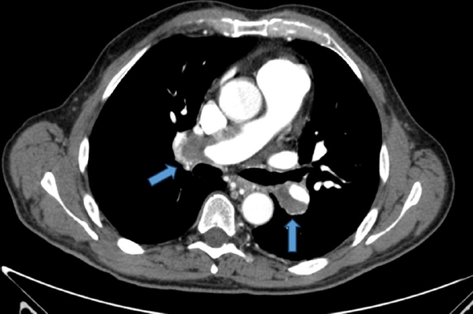

Presentamos el caso de un varón de 58 años diagnosticado de hipertensión pulmonar tromboembólica crónica (HPTEC), sometido a cirugía de endarterectomía pulmonar (EAP) bilateral, con excelente resultado. El paciente, con antecedente de hipertensión arterial bien controlada, con tratamiento con antagonistas de los receptores de la angiotensina II, consultó por astenia y disnea de varios meses de evolución, que había ido en aumento hasta hacerse de mínimos esfuerzos, presentando 7 días antes de su ingreso un episodio de mareo intenso. Su estado general era bueno, con adecuada perfusión de la piel y las mucosas. En la exploración física, la tensión arterial era de 120/64 mmHg, la frecuencia cardiaca de 65 lpm y la respiratoria de 14 rpm. Presentaba ventilación pulmonar conservada y un soplo sistólico en foco tricuspídeo, grado II/IV, sin irradiación y con segundo tono normal en la auscultación cardiaca. La radiografía de tórax mostró una silueta cardiomediastínica dentro de la normalidad, y sin datos de enfermedad pleuropulmonar. En el electrocardiograma se advertía un ritmo sinusal con extrasístoles auriculares aisladas. La saturación arterial de oxígeno (SpaO2) era del 94,2%, con una presión parcial de O2 de 68,0 mmHg y una presión parcial de CO2 de 34,0 mmHg. La determinación del dímero D resultó normal. La angiotomografía computarizada (angio-TC) torácica evidenció defectos de repleción en ambas arterias pulmonares principales, compatible con trombo crónico (Fig. 1). La eco-Doppler de miembros inferiores no mostró datos de trombosis venosa profunda. Se practicó un ecocardiograma Doppler que mostró un ventrículo izquierdo con diámetros normales con función global conservada, así como una insuficiencia tricuspídea (IT) moderada y una presión sistólica pulmonar estimada (PSAPe) de 125 mmHg, con moderada dilatación de cavidades derechas. El paciente fue diagnosticado de hipertensión pulmonar (HP) secundaria a embolia pulmonar (EP) crónica y tratada con anticoagulación. En el seguimiento a los 3 meses, el paciente mantenía disnea clase III de la World Health Organization (WHO), y en la ecocardiografía Doppler cavidades derechas moderadamente dilatadas con una IT leve y una PSAPe de 75 mmHg. El estudio de hipercoagulabilidad resultó normal. El paciente fue sometido al protocolo diagnóstico de HPTEC: se practicó una gammagrafía de perfusión pulmonar que mostró múltiples defectos de perfusión intrapulmonares en segmentos superior e inferior de ambos campos pulmonares, hallazgos compatibles con alta probabilidad de EP; la espirometría mostró una limitación ventilatoria restrictiva de grado moderado; la prueba de marcha de los 6 min (PM6M), realizada en aire ambiente, mostró una distancia total recorrida de 400 m, SpaO2 basal del 94% y SpaO2 final del 88% (puntuación 7 en la escala Borg); el cateterismo cardiaco derecho confirmó una presión media arterial pulmonar (PmAP) de 47 mmHg; y finalmente, se realizó una arteriografía digital pulmonar que mostró defectos de vascularización centrales en ambos pulmones, y una coronariografía que descartó enfermedad arterial coronaria. Previa implantación de un filtro de Greenfield en la vena cava inferior, se practicó al paciente una EAP bilateral mediante esternotomía media, con apoyo de circulación extracorpórea y periodos de parada circulatoria intermitente en hipotermia profunda (Fig. 2). No se produjeron complicaciones posoperatorias. En el control a los 90 días, tras la cirugía, el paciente se encontraba en clase funcional I de la WHO con una SpaO2 del 99%, respirando aire ambiente. La nueva PM6M mostró una distancia total recorrida de 470 m y una SpaO2 basal del 99% con una SpaO2 final del 94% (puntuación 1 en la escala de Borg). El estudio de la función pulmonar resultó normal y el ecocardiograma Doppler mostró una PSAPe de 35 mmHg, con cavidades derechas de tamaño normal. En la angio-TC torácica no se identificaron defectos de repleción intravasculares (Fig. 3). Todos los pacientes con HPTEC deben recibir anticoagulación indefinida con el fin de prevenir la trombosis in situ y el tromboembolismo recurrente1. La cirugía de EAP es el tratamiento de elección de la HPTEC, en los casos en que se estime que esta intervención permitirá la extracción de una cantidad significativa de material fibrotrombótico de las arterias pulmonares. La EAP es el único tratamiento que puede lograr la curación de la HPTEC, y es apropiada para más del 60% de los pacientes. La EAP consiste en la extracción quirúrgica del material trombótico intravascular organizado, la capa íntima engrosada, a la cual aquel está firmemente adherido, y parte de la capa muscular. La endarterectomía debe ser bilateral y completa, es decir, extirpando el material fibrotrombótico más periférico. Para ello se requiere esternotomía media, circulación extracorpórea y pausas de parada circulatoria completa que permitan visualizar adecuadamente el árbol vascular. Para evitar el posible daño cerebral durante la parada circulatoria, estas se limitan a una duración menor de 20 min por lado, y se realizan en hipotermia profunda de entre 18-20 ◦C. La intervención proporciona unos excelentes resultados, con un porcentaje de curación de la HP (valor de PmAP posoperatorio < 25 mmHg) cercano al 50%, mejoría de la hemodinámica y de la tolerancia al esfuerzo francas, y buena supervivencia a largo plazo2. La EAP no está exenta de complicaciones y requiere de experiencia, tanto del procedimiento quirúrgico como del manejo perioperatorio. La mortalidad en el periodo posoperatorio en los centros con mayor experiencia es actualmente del 4-5%. En un registro en el que se incluyeron 386 pacientes de 26 centros expertos europeos y uno canadiense, la mortalidad en el posoperatorio inmediato fue del 4,7%. Las complicaciones posoperatorias más frecuentes son el edema de reperfusión y la HP persistente tras la cirugía. La decisión debe ser individualizada para cada paciente, puesto que en el éxito de la cirugía interviene la relación que existe entre las lesiones trombóticas accesibles quirúrgicamente y el estado hemodinámico, la función del ventrículo derecho, la edad del paciente y las comorbilidades, entre otros factores. La angioplastia con balón de las arterias pulmonares es una técnica que se ha postulado en los últimos años, y que se podría tener en cuenta para pacientes que se consideran inoperables debido a enfermedad predominantemente distal o a enfermedades asociadas o en aquellos pacientes con HP persistente o recurrente después de la EAP.

Figura 1 Angio-TC torácica, en la que se aprecian defectos de repleción en ambas arterias pulmonares principales, compatible con tromboembolismo pulmonar.